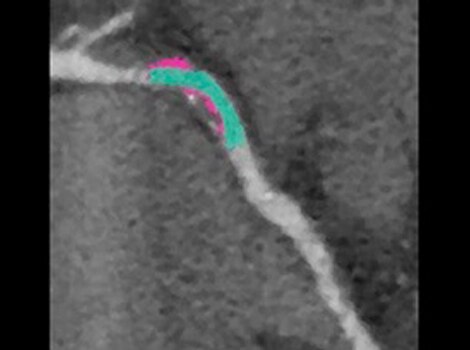

3D Heart

借助鲜血、3D 序列实现解剖结构和心脏血管的可视化。

借助鲜血、3D 序列实现解剖结构和心脏血管的可视化。了解更多信息